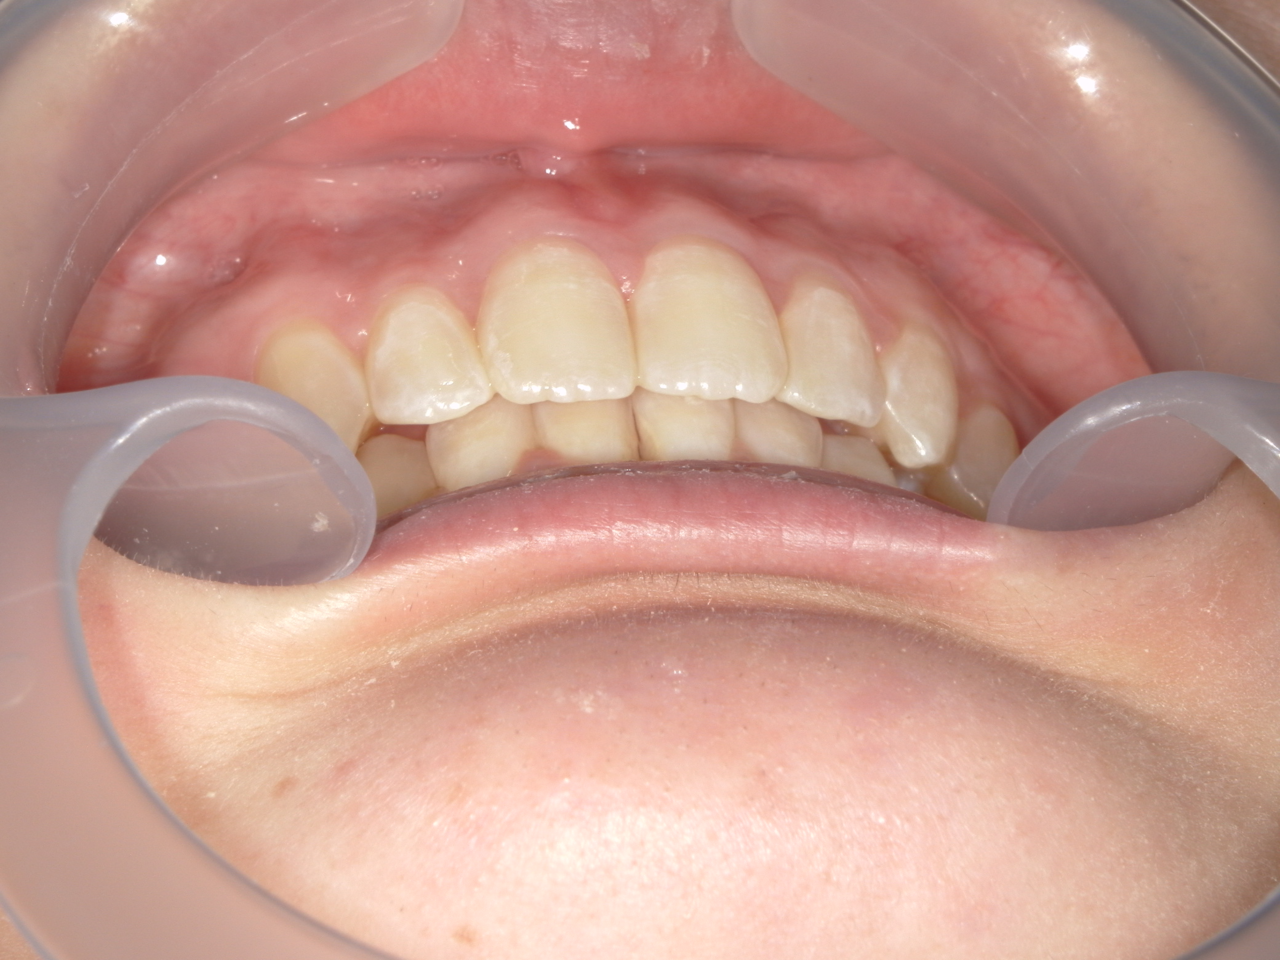

治療前

治療説明 歯科矯正でも目立ちにくい矯正方法であるマウスピース矯正で治療しました

治療期間 2年6か月

治療費用498000 円

治療後

治療の副作用(リスク)歯の動き方には個人差があり、予想された治療期間が延長する可能性があります。。マウスピースの使用状況、矯正歯科治療には患者さんの協力が必要であり、それらが治療結果や治療期間に影響します